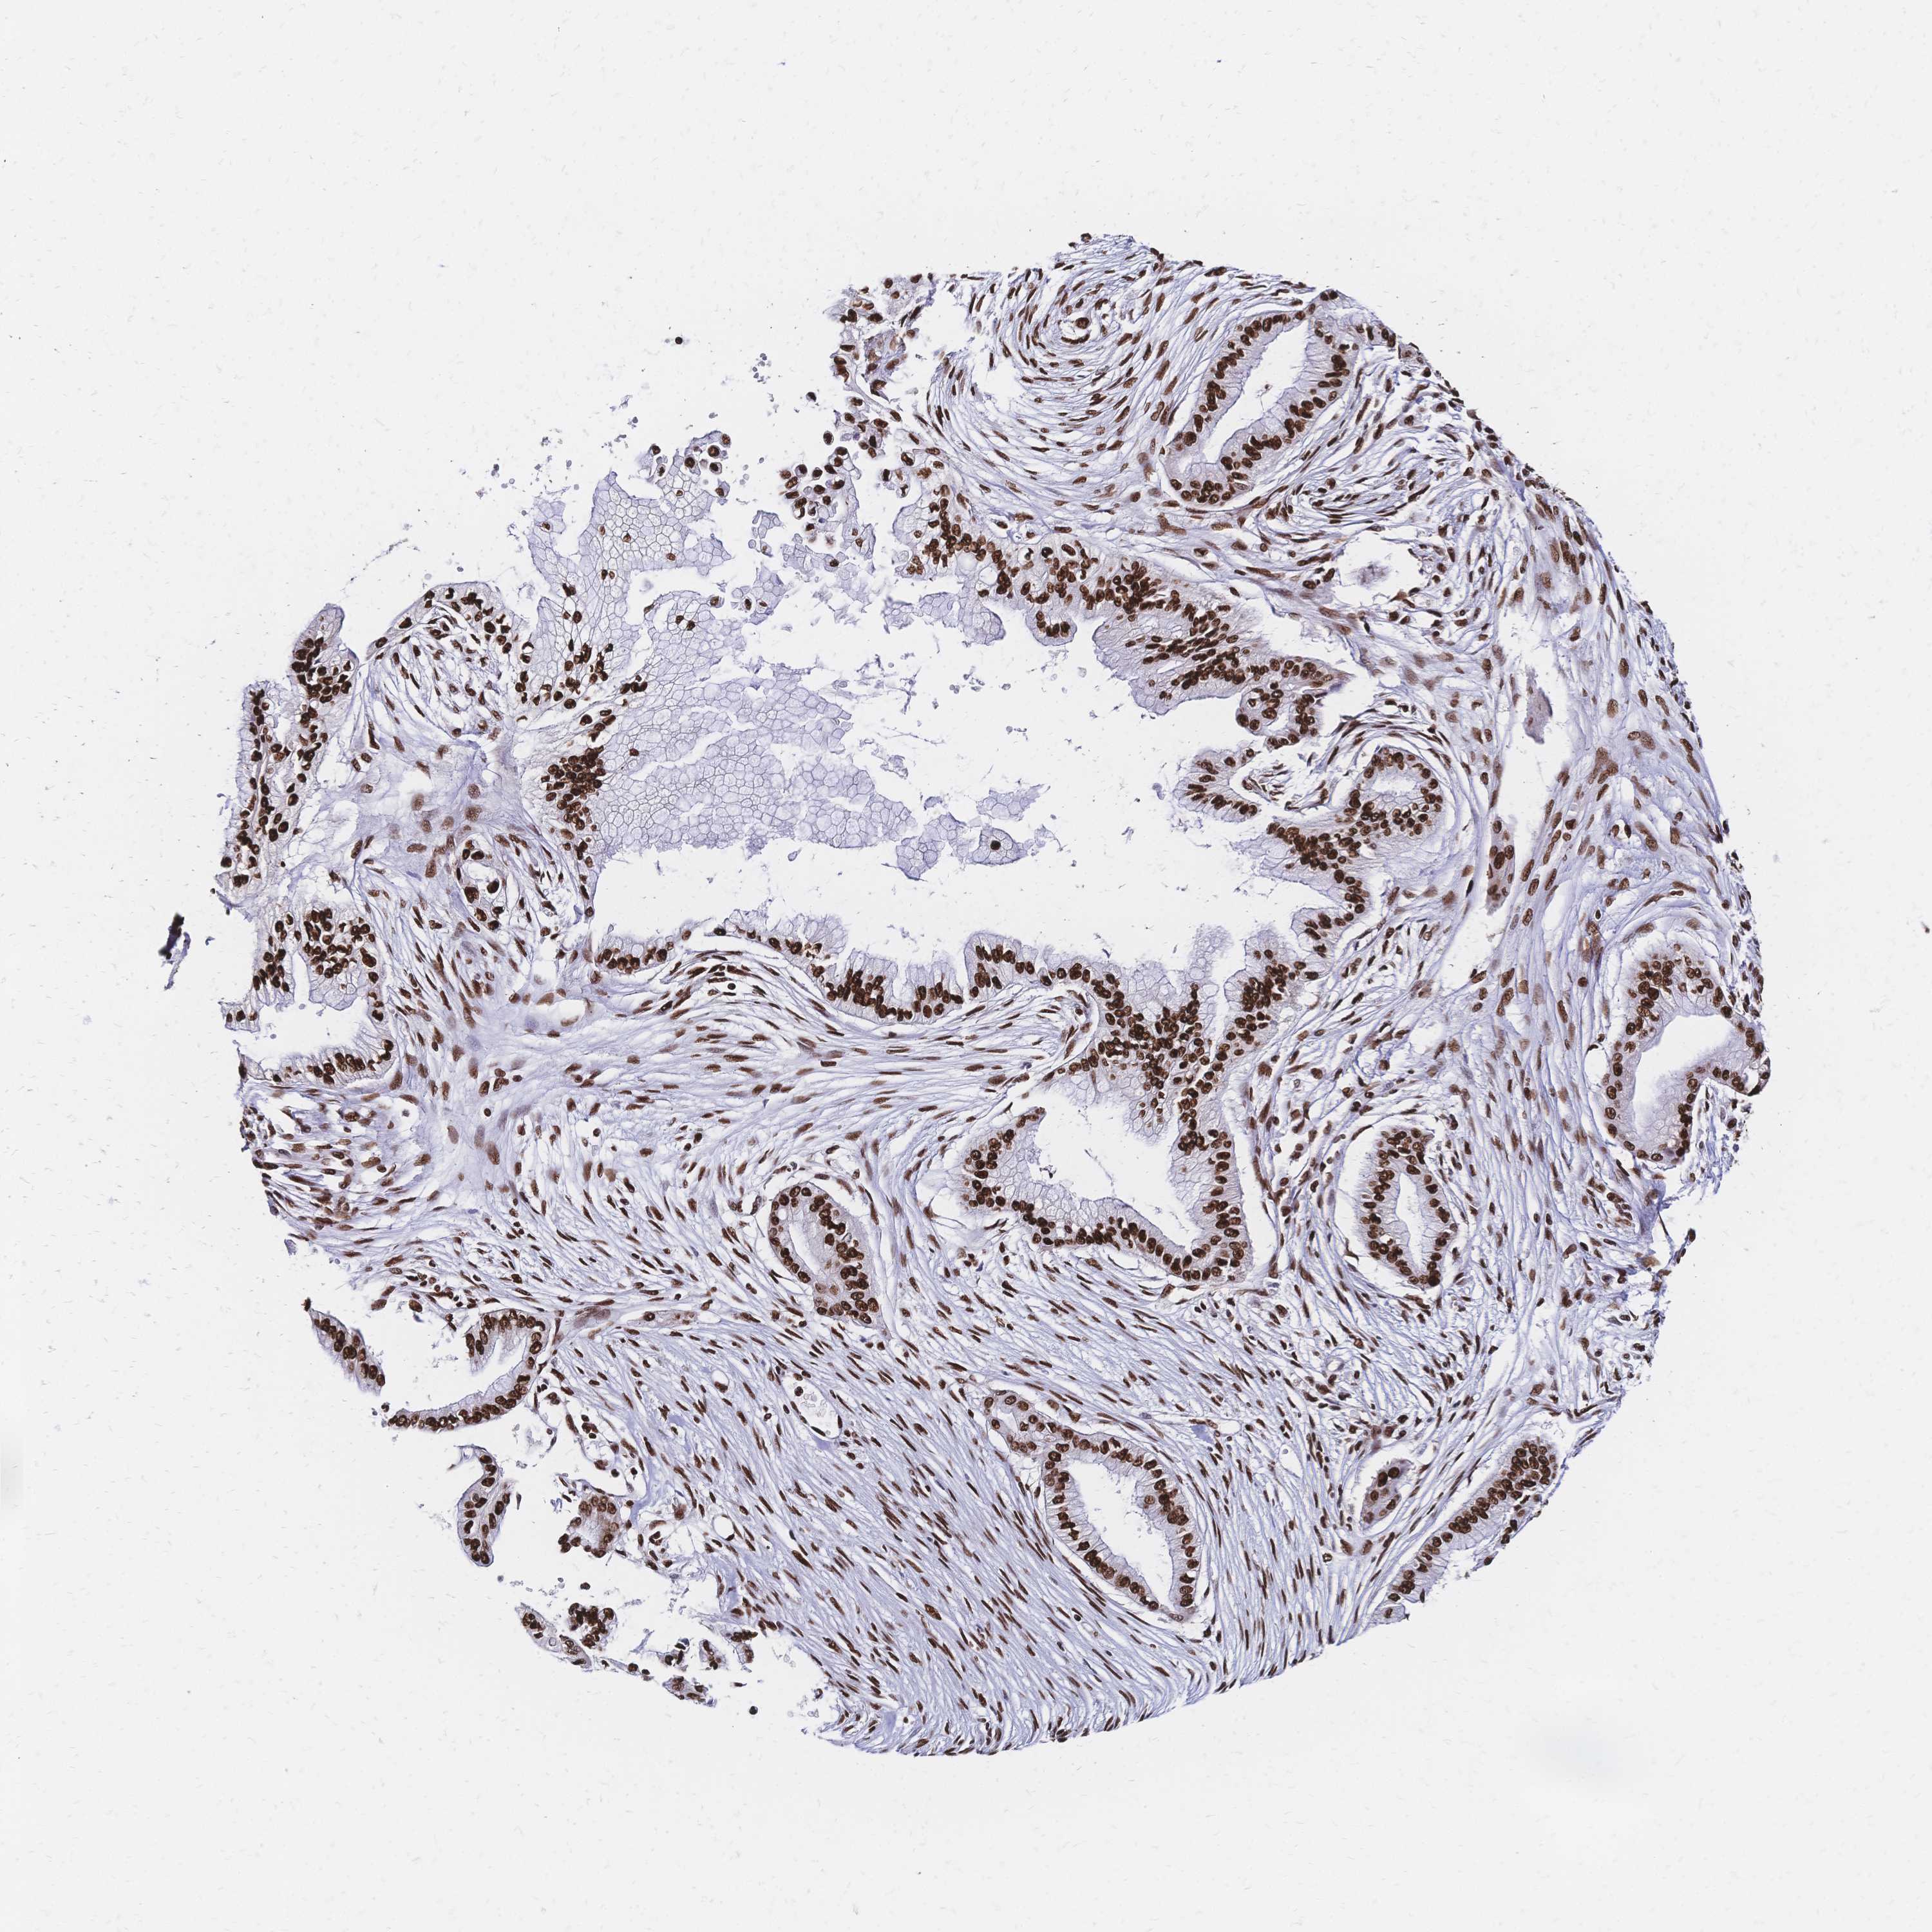

PANCREATIC CANCER - Protein expressioni

A mouse-over function shows sample information and annotation data. Click on an image to view it in a full screen mode. Samples can be filtered based on level of antibody staining by selecting one or several of the following categories: high, medium, low and not detected. The assay and annotation is described here.

Note that samples used for immunohistochemistry by the Human Protein Atlas do not correspond to samples in the TCGA dataset.

Antibody stainingi

Antibody staining in the annotated cell types in the current human tissue is reported as not detected, low, medium, or high, based on conventional immunohistochemistry profiling in selected tissues. This score is based on the combination of the staining intensity and fraction of stained cells.

Each image is clickable and will lead to virtual microscopy that enables deeper exploration of all samples and also displays staining intensity scores, fraction scores and subcellular localization as well as patient and tissue information for each sample.

Antibody HPA048728

Antibody HPA053422

Antibody CAB026035

Staining

High

Medium

Low

Not detected

Intensity

Strong

Moderate

Weak

Negative

Quantity

>75%

75%-25%

<25%

None

Location

Nuclear

Cytoplasmic/membranous

Cytoplasmic/membranous,nuclear

Adenocarcinoma, NOS